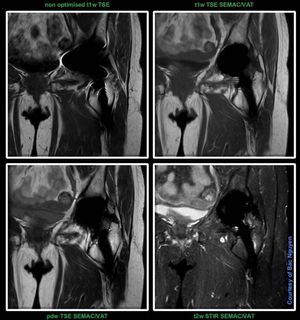

Advanced WARP @ Siemens 1.5T Aera First version of metal reduction sequences was WARP. WARP provided inplane metal reduction with View Angle Tilting (VAT). Later Advanced WARP came along which provided both inplane and through plane metal reduction. VAT for the inplane, while SEMAC for the through plane. Just a test I did here on a prosthesis. I don’t know if an old school approach would be equivalent or even better than SEMAC/VAT. Old school wasn’t tested in this case.#Siemens_MRI #siemens #mri #advanced_warp